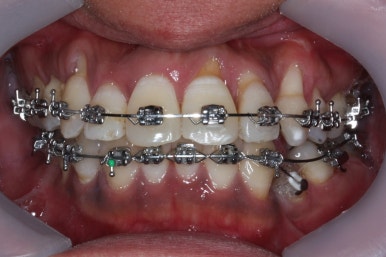

드디어 치료 종료시의 모습입니다. 2년 4개월 걸렸네요.

앞니 안쪽에는 유지철사를 붙여주었고요. 임플란트가 필요한 부위랑 맞닿은 부분은 치열이 움직이지 않도록 철사로 잡아주었어요.(오른쪽 어금니 부위)

삐뚤었던 치아들이 가지런해졌습니다.

왼쪽 송곳니를 발치했지만 별로 표시가 안나게 마무리를 했습니다.

많이 썩은 치아들은 다 뽑았고, 틈새도 다 다물어졌습니다.

원래 패여 있던 부위는 완벽하게 만들기는 힘들지만 앞으로 관리를 잘해주시면 이 모습 그대로 오래 사용하실 수 있으실거에요.